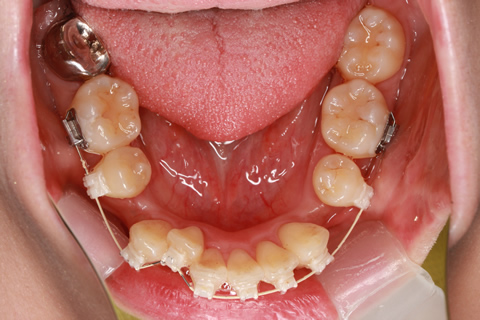

矯正期間18ヶ月

フルリンガル矯正2(上下の歯を舌側矯正で治療)

治療前

治療中

治療後

- 年齢・性別

- 42歳男性

- 治療期間

- 1年6ヶ月

- 抜歯

- なし

- 治療費

- 120万円(税込み)

- マルチブラケットを用いた矯正治療

- 治療内容

- 反対咬合をフルリンガル矯正治療にて改善

- 施術の副作用(リスク)

- 表側矯正と比較して、歯根の角度を確立する「トルク」の力がかかりにくい。